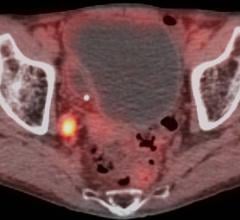

Bridget F. Koontz, M.D., chief medical officer at GenesisCare USA explains how to manage the complex needs of pelvic ...